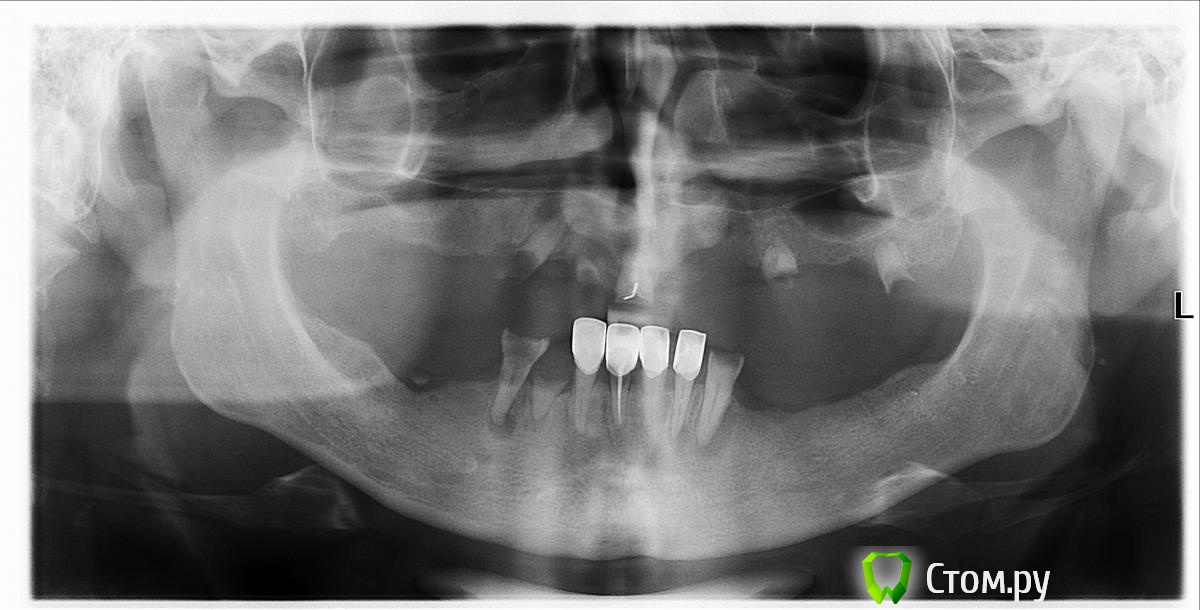

andr112176 Опубликовано 31 марта, 2014 Поделиться Опубликовано 31 марта, 2014 Добрый день! Есть вопрос, очень болезненный, во всех смыслах)) Доктор предлагает удаление всех зубов и ставить сразу по 6-ть имплантов (имплантатов) в каждую челюсть, а затем установить на них условно-съемные протезы (через 4 месяца). Кости говорит мало, но попробуем. Систему имплантации предлагает "IMPRO". Вопросы в общем то следующие, хватит ли кости судя по снимку, явные очаги воспаления. хочется мнение услышать людей профессиональных в данных вопросах, деньги немалые.. а то мне, дилетанту наговорить можно многое.. Ссылка на комментарий

Bier Опубликовано 31 марта, 2014 Поделиться Опубликовано 31 марта, 2014 сделать это можно. Только внизу на 6ти имплантатах вполне можно сделать несъемную конструкцию.а для условно съемной наверху достаточно 4х. Если наверх тоже хочется несъемную конструкцию, тогда придется нарастить кость и поставить 6-8 имплантатов. Ссылка на комментарий